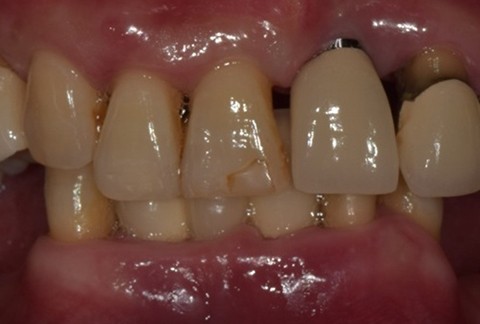

임플란트-보철-시-기성-어버트먼트가-아닌-맞춤-지대주-사용-보철-파절-위험-방지-음식물-끼임-방지-주위염-방지-맞춤-지대주는-환자의-구강환경에-맞는-교합을-구현할-수-있고-앞니-보철시-더욱-심미적으로-제작이-가능합니다

임플란트-전후사진